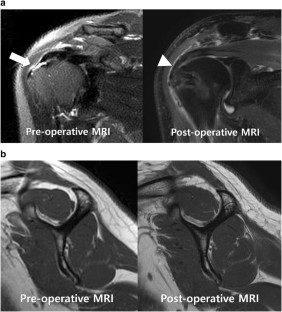

Fig. 3